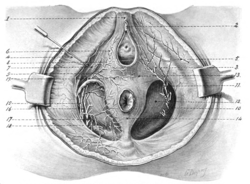

1, Suspensory ligaments of clitoris; 2, glans clitoridis ; 3, posterior superficial perineal nerve; 4, fascia lata; 5, inferior pudendal nerve; 6, sphincter vaginac muscle ; 7, erector clitoridis muscle; 8, superficial perineal artery; 9, transverse perineal artery ; 10, obturator fascia; 1 1, anterior superficial perineal nerve ; 12, anal fascia; 13, deep layer of superficial fascia ; 14, external sphincter ani muscle; 15, dorsal nerve of clitoris ; 16, internal pudic artery ; 17, perineal | |

Dissection of the female perineum